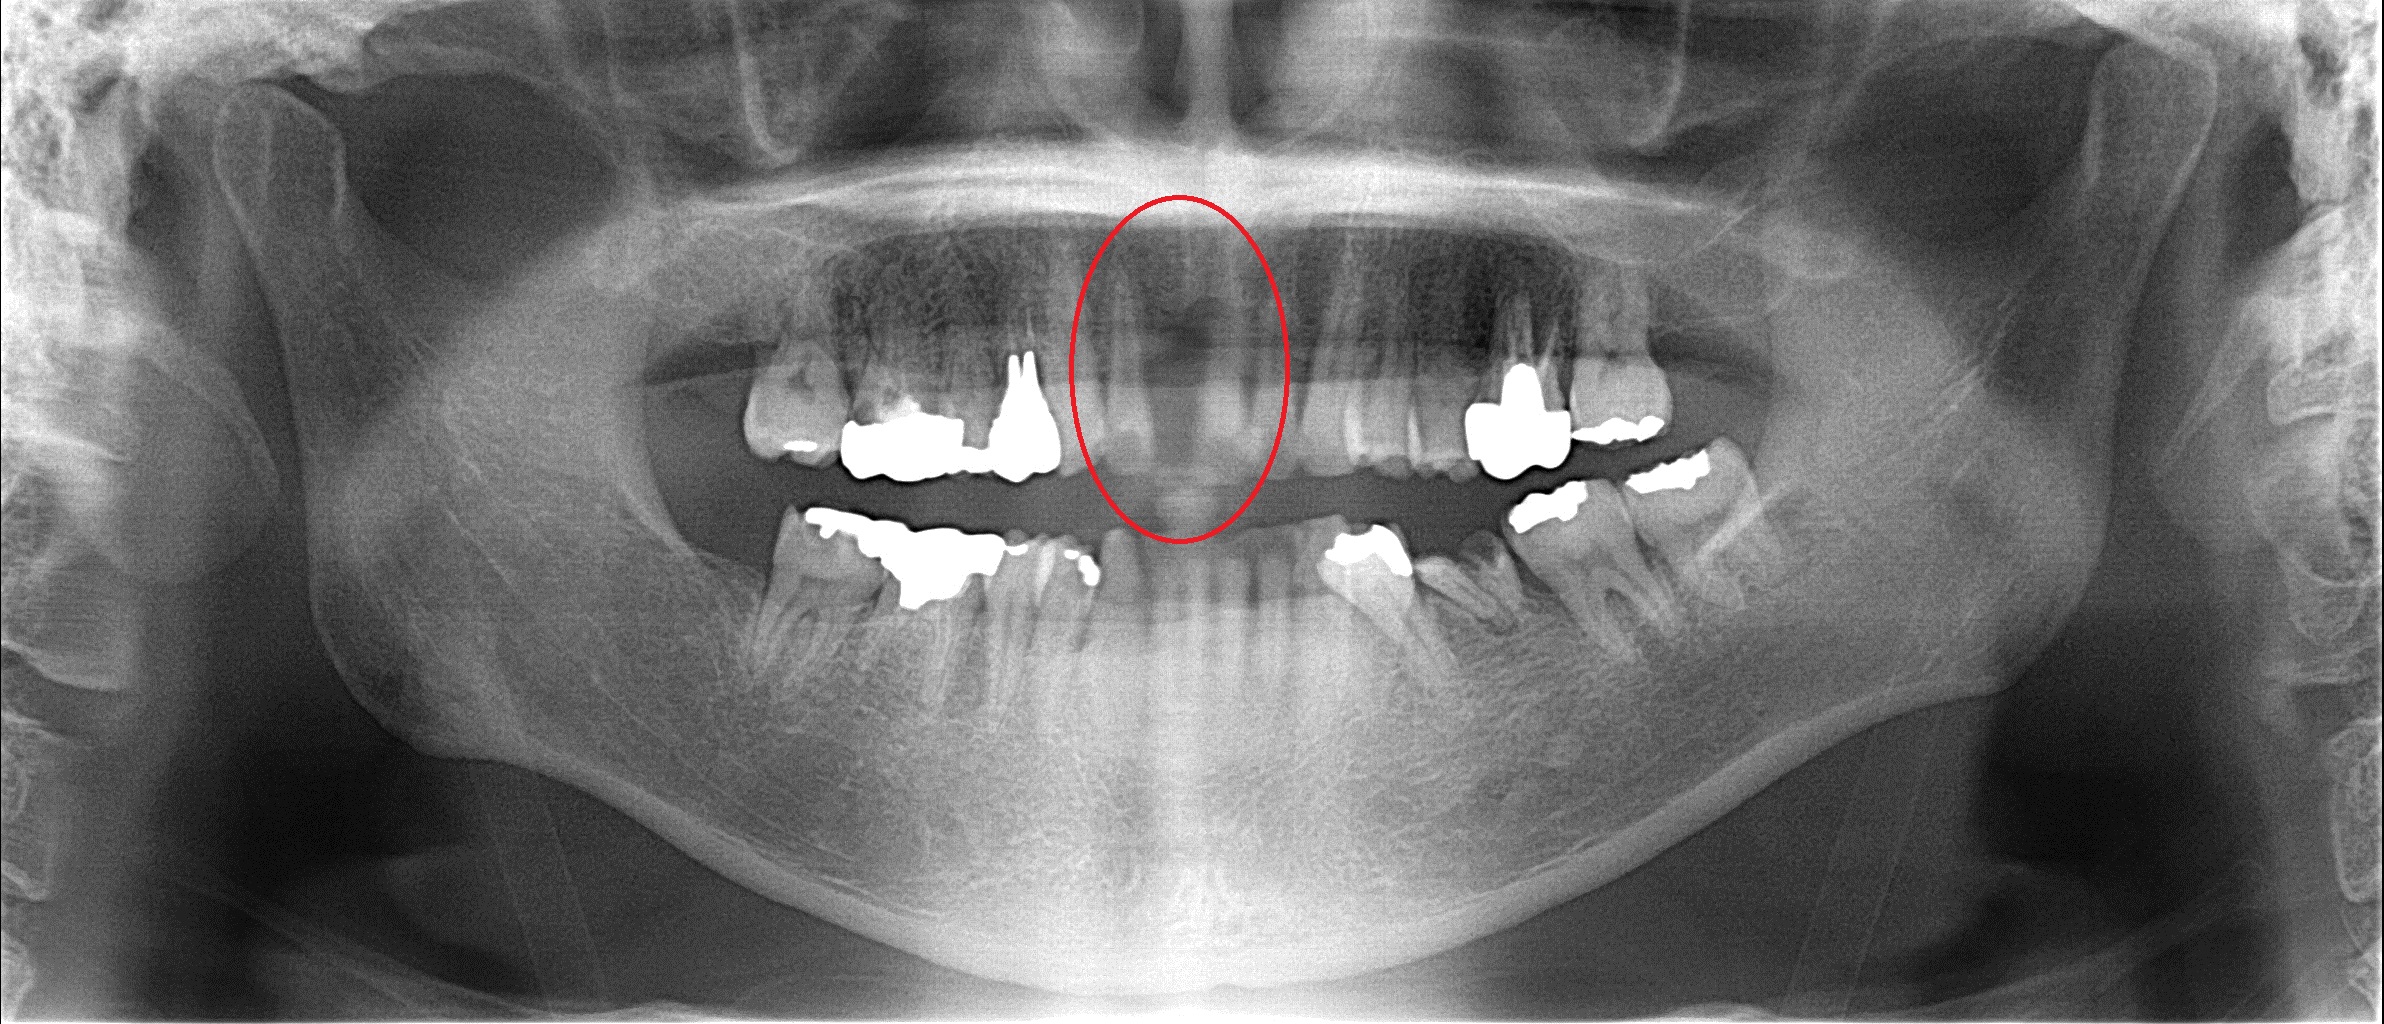

来院時のレントゲン 赤い丸の部分の歯がありません。